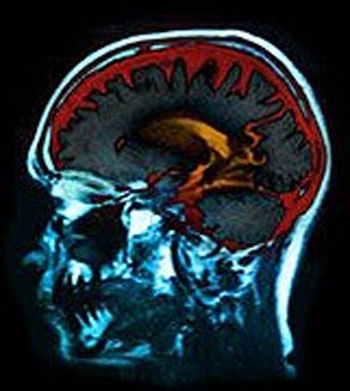

Nghiên cứu được công bố ngày 2/8 trên tờ Neurology này cho thấy: Những người tham gia được kiểm tra mức độ tiểu đường, cholesterol, huyết áp, trọng lượng cơ thể và vòng eo. Họ cũng được chụp cắt lớp não MRI trong thời gian nghiên cứu khoảng 10 năm.

Kết quả nghiên cứu cho thấy những người huyết áp cao sẽ đẩy nhanh tốc độ tổn thương mạnh máu não hơn so với những người có huyết áp bình thường. Những người mắc bệnh tiểu đường và hút thuốc ở tuổi trung niên thì có sự co não và mất tế bào não ở vùng đồi thị nhanh hơn đồng thời làm gia tăng những tổn thương ở các mạch máu não so với những người không mắc tiểu đường và không hút thuốc.